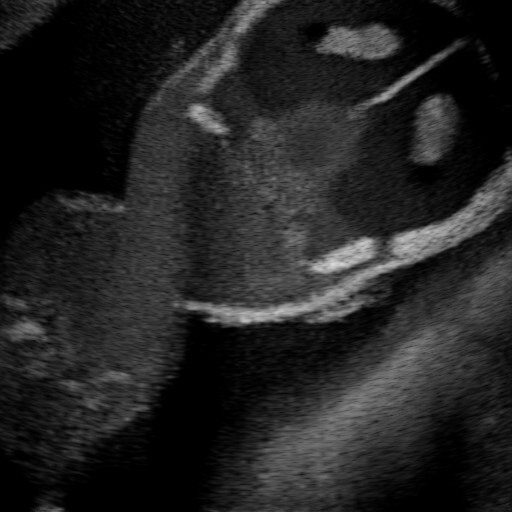

Qualitative Results. Fig. 3 shows a visual comparison of the three model variants on four examples. The baseline L2HM fails to preserve anatomical structures due to missing structural information in the input images. Resulting ambiguities in the network prediction cause artifacts such as blur in regions that feature fine details such as bones. Providing segmentation maps as additional input (L2HMS) greatly reduces such artifacts as shown in Fig. 3(c). However, L2HMS still struggles in modeling complex non-local features such as directional occlusion artifacts, note the lack of acoustic shadows in Fig. 3(c). In contrast, our final model L2HMSA is able to accurately synthesize these features and produces translations significantly closer to the target, as demonstrated in Fig. 3(d). In particular, our proposed model with segmentation and attenuation integral maps is able to recover both missing anatomical structures and directional artefacts.

(a) Input

(b) L2HM

(c) L2HMS

(d) L2HMSA

(e) Target